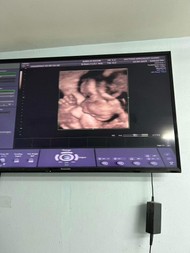

ขอดูรูปซาว3มิติของแม่ๆหน่อยค่ะ ซาวตอนกี่วีคกันบ้าง #ขอบคุณสำหรับคำตอบค่ะ

3มิติ ตอน25wค่ะแม่